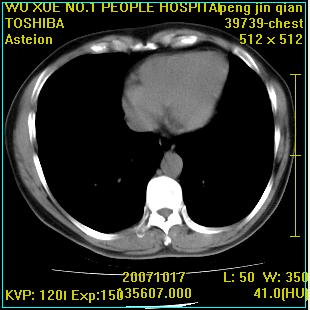

标题: CT10148:男,56岁,咳血。 [打印本页]

标题: CT10148:男,56岁,咳血。

右肺下叶背段/左上肺/左下肺结核伴空洞形成

结核 空洞伴两肺播散

浸润型肺结核伴左上肺空洞形成,两肺播散灶